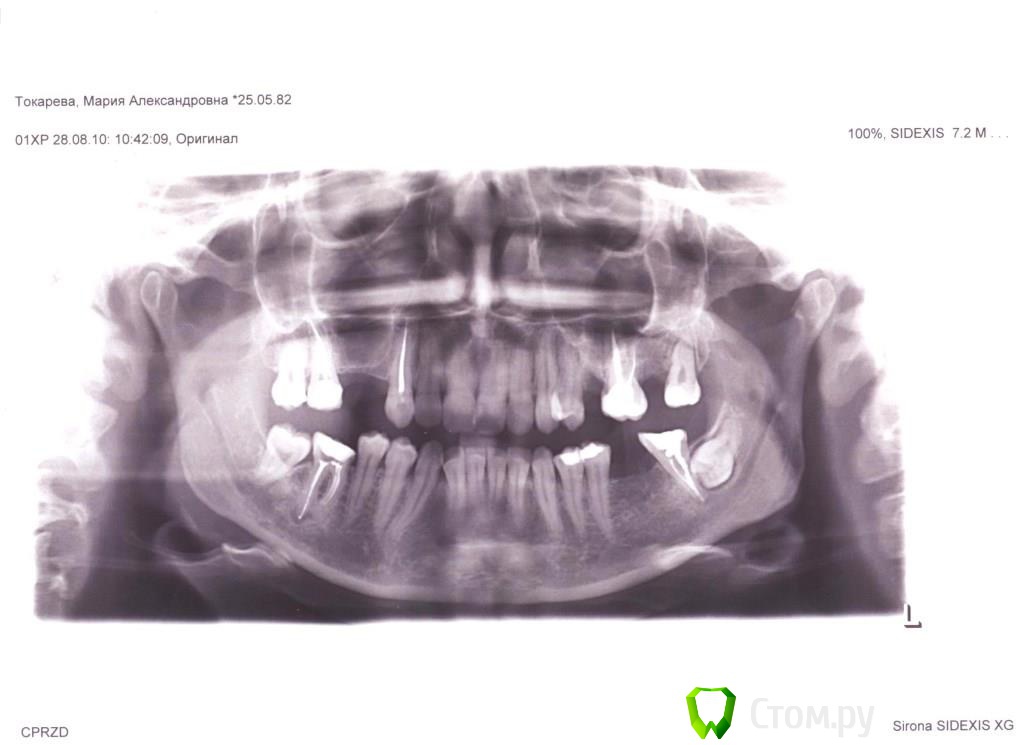

pupsenok Опубликовано 13 декабря, 2013 Поделиться Опубликовано 13 декабря, 2013 (изменено) Добрый день уважаемые врачи!Вопрос на повестке для стоит такой: заканчиваю лечение брекетами, пора приступать к протезированиюэ.Сходила на пару консультаций и тут возникли разногласия: - кто то говорит о мостах, мотивируя долгоиграющую еще возню с имплантами и синуслифтингом, да и последствиями непредсказуемы, - кто то пропрочит импланты, ибо это современно,эстетично и вообще все будет хорошо.Прошу Вашего профессионального вывода и аргументов, ибо решать вопрос надо, и надо как то определится в ближайшее время, пока обратно зубья не полезли)Прилагаю два снимка, нынешний ( за качество извиняюсь), и что было ( может будет интересно).Большое спасибо заранее, за уделенное мне время! Изменено 13 декабря, 2013 пользователем pupsenok Ссылка на комментарий

Igor3252 Опубликовано 15 декабря, 2013 Поделиться Опубликовано 15 декабря, 2013 Мосты- время революции . Судя п0 последнему снимку-14,15 имплант . Либо один между 14-15 и на него две коронки. Нужно смотреть расстояние по к/т Нижнюю левую 8 убрать однозначно .. ( минут 30 ) 36 имплант .. И не нужны Вам никакие мосты . Это сугубо мое IMHO Ссылка на комментарий